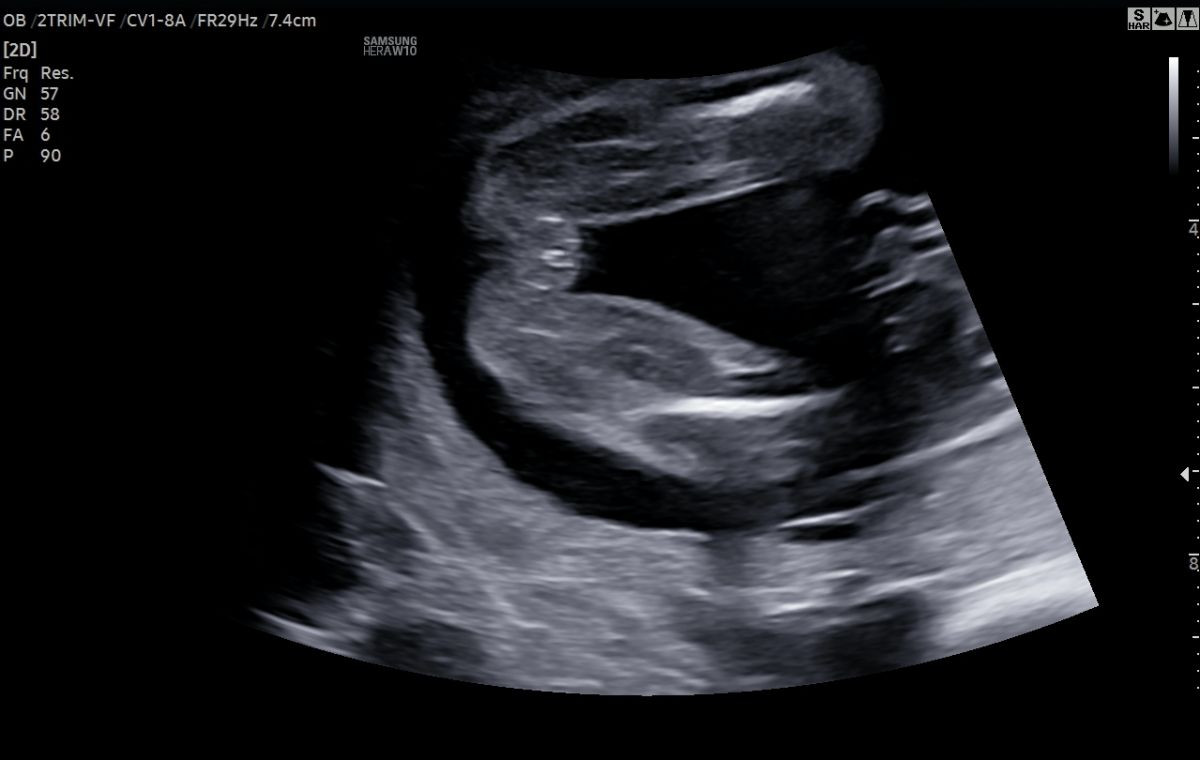

Určení pohlaví miminka

Cílem ultrazvukového určení pohlaví miminka je sdělit vám, zda můžete očekávat narození holčičky či chlapečka.

Určit s jistotou správné pohlaví miminka je ultrazvukem možné od 16. týdne těhotenství. Před 16. týdnem vypadá pohlaví holčičky a chlapečka velmi podobně a hrozí podání chybné informace.